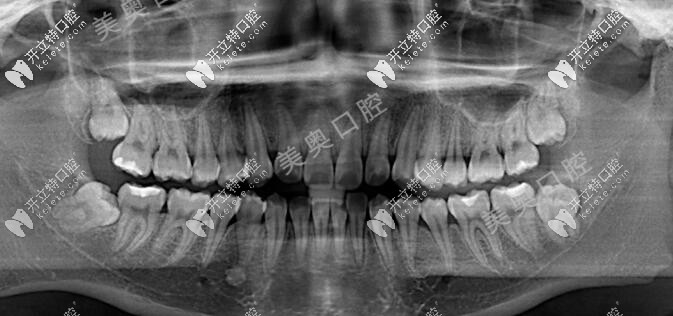

從口內(nèi)照片可以看出來,牙列存在擁擠情況,且中線不齊,X線片顯示顧客的四顆智齒也是正在萌出,位置相對比較正常,牙弓有輕微的2mm擁擠,矯正前的左右面容也不對稱。